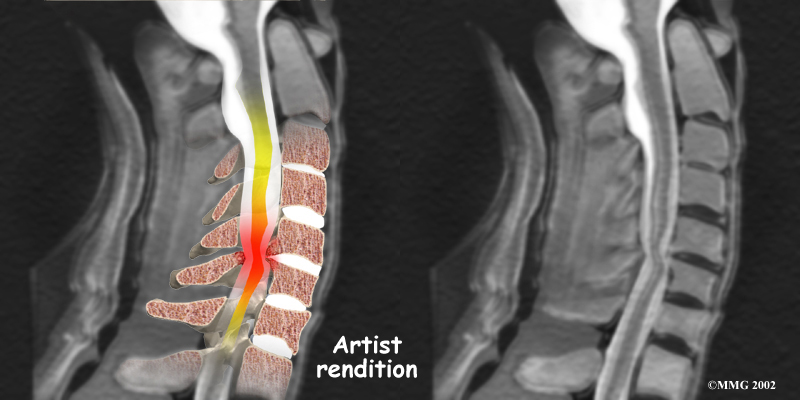

Stenosis means closed in. Spinal stenosis refers to a condition in which the spinal cord is closed in, or compressed, inside the tube of the spinal canal. Spinal stenosis may be caused by degenerative changes, such as bone spurs pushing against the spinal cord within the spinal canal.

Spinal Stenosis

However, stenosis can also develop when a person of any age has a disc herniation that pushes against the spinal canal. When the spinal cord is squeezed in the neck, doctors call the condition cervical myelopathy. This is an alarming condition that demands medical attention. Cervical myelopathy can cause problems with the bowels and bladder, change the way you walk, and affect your ability to use your fingers and hand.